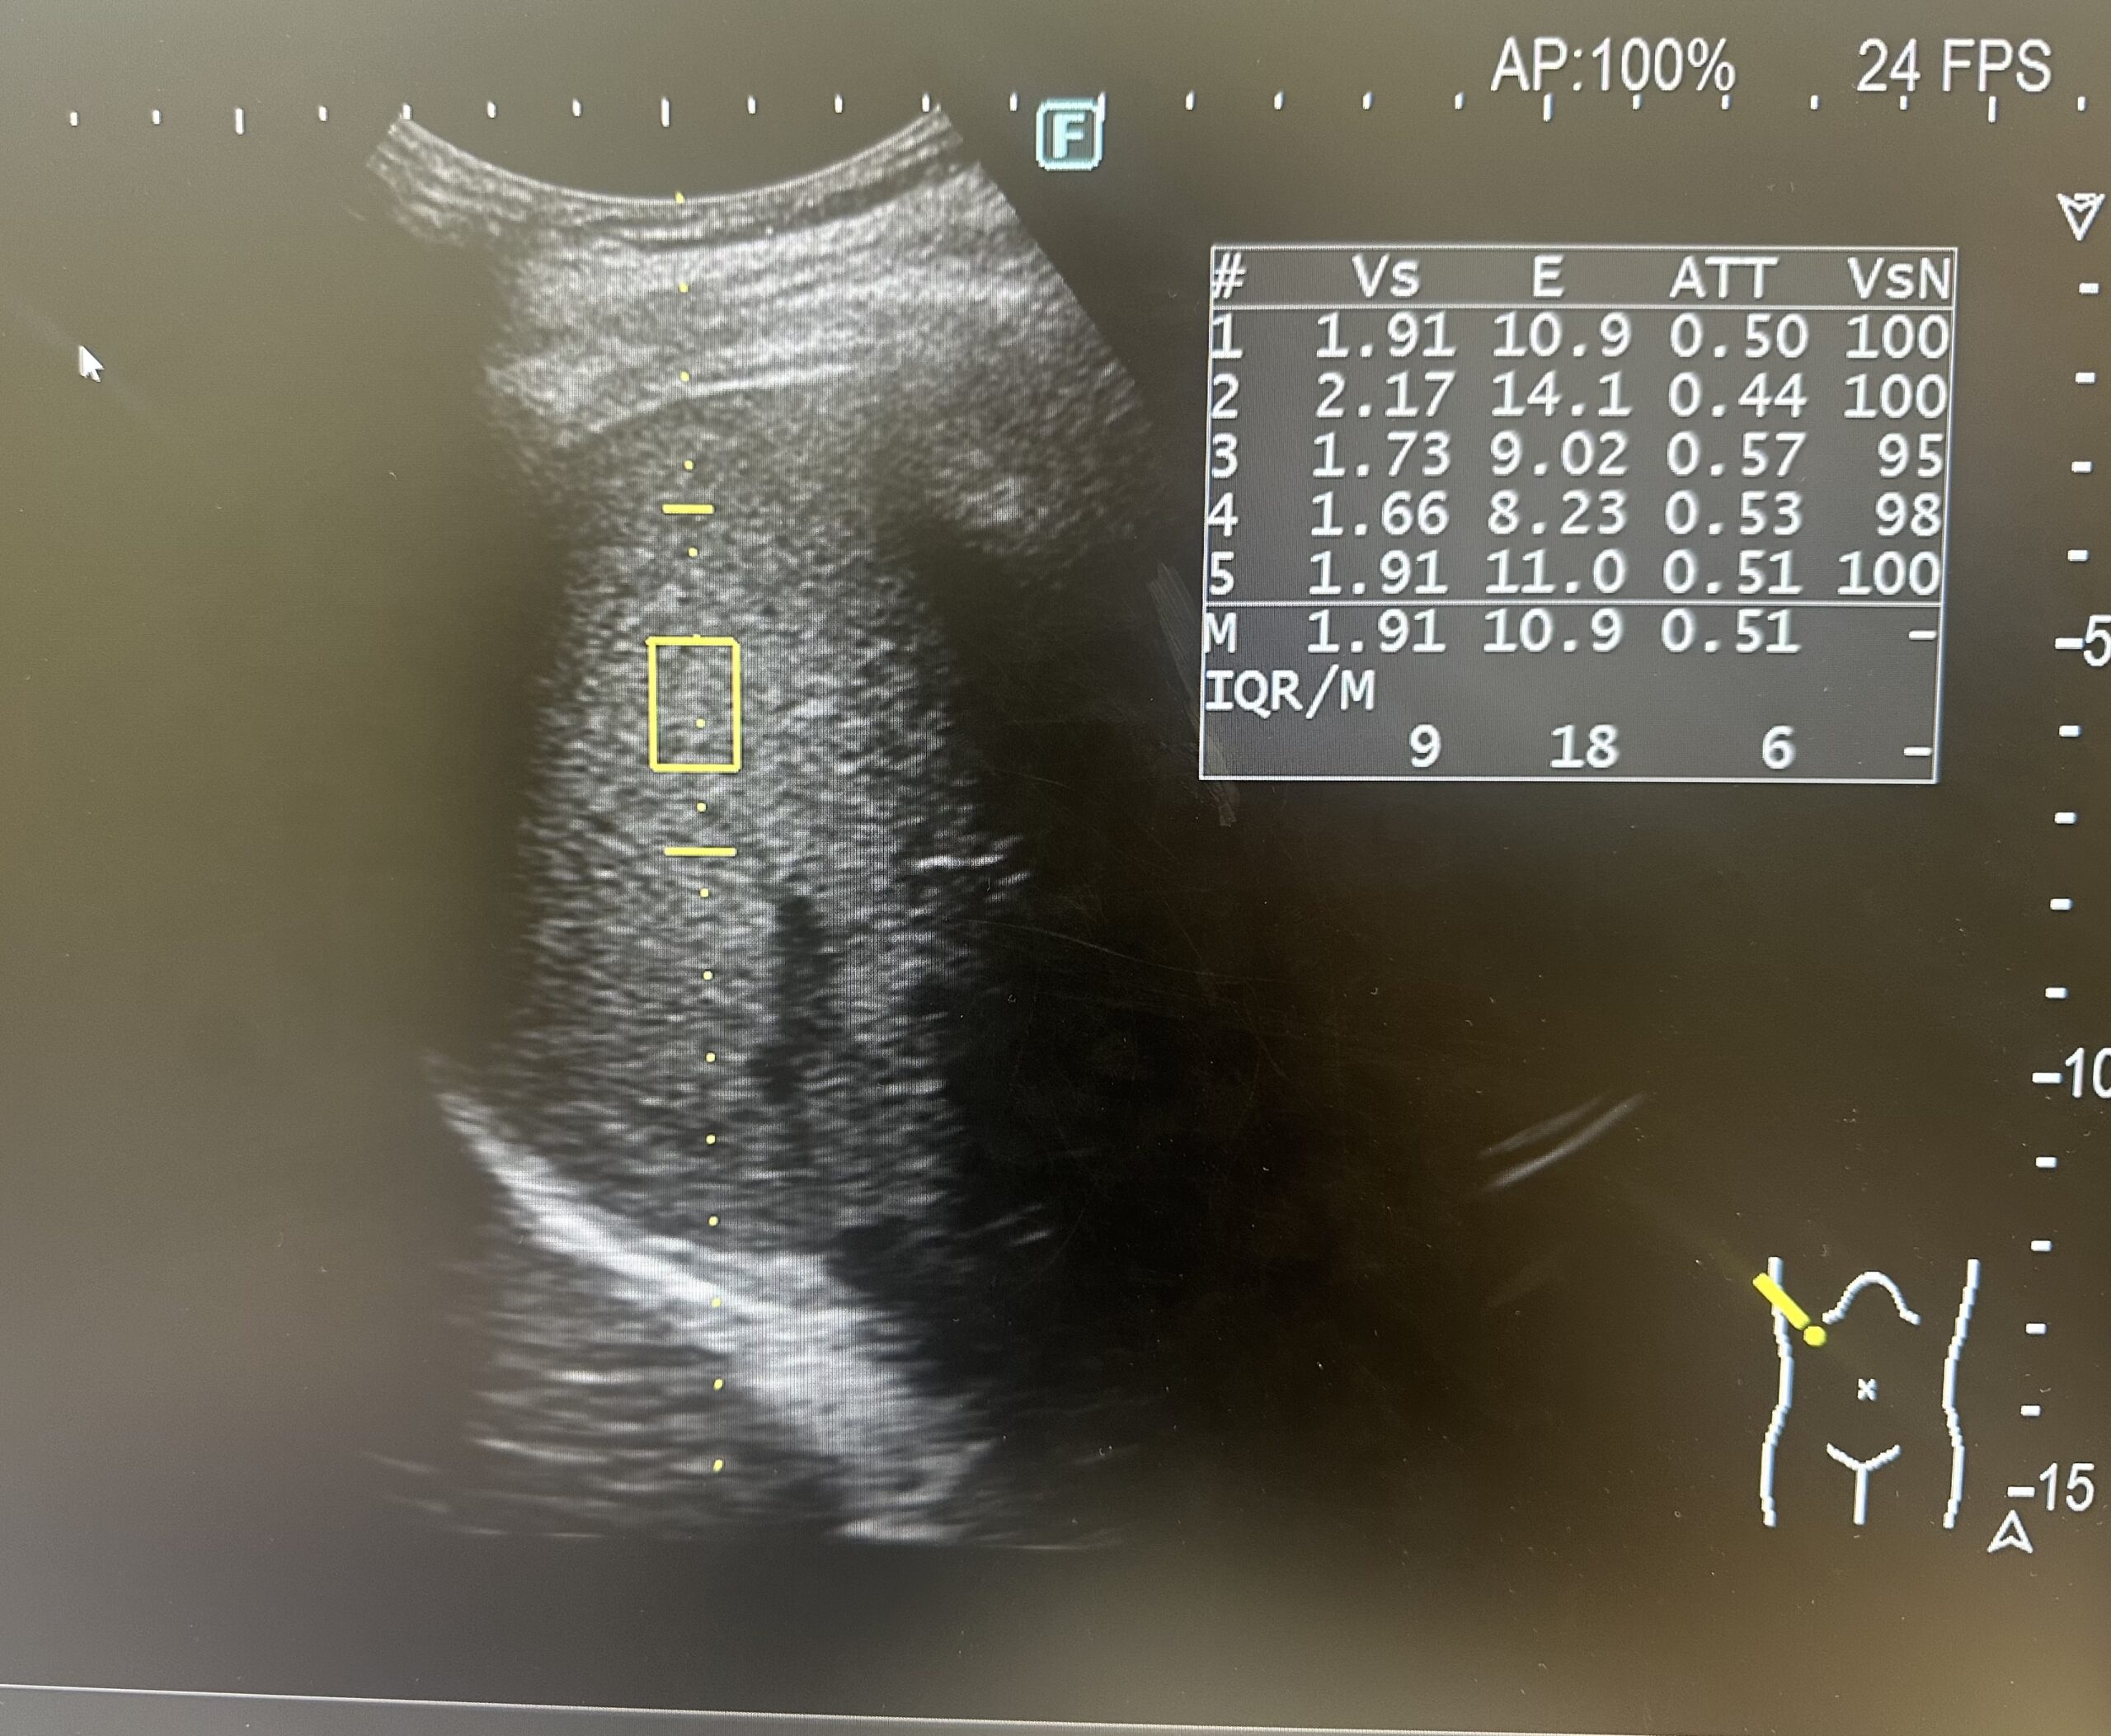

肝障害などによりおこなう腹部エコーで、必要に応じて肝硬度と脂肪化を測定します。測定した場合はレポートに下のような画像が添付されています。

VsおよびE

肝臓の繊維化の進行と共に増加する数値。肝臓の繊維化の評価に使用します。

この数字が高い場合は肝臓の繊維化が疑われます。

Vs(m/s)1.441.541.641.91

E(kPa)6.187.098.0510.89

VsN

Vs計測の信頼性の指標です。この数値が高ければ信頼性の高い検査結果です。

ATT

肝臓の減衰の評価に使います。正常が0.5dB/cm/MHzですが、脂肪組織が多くなると上昇します。

S1S2S3

ATT<0.68<0.73<0.75